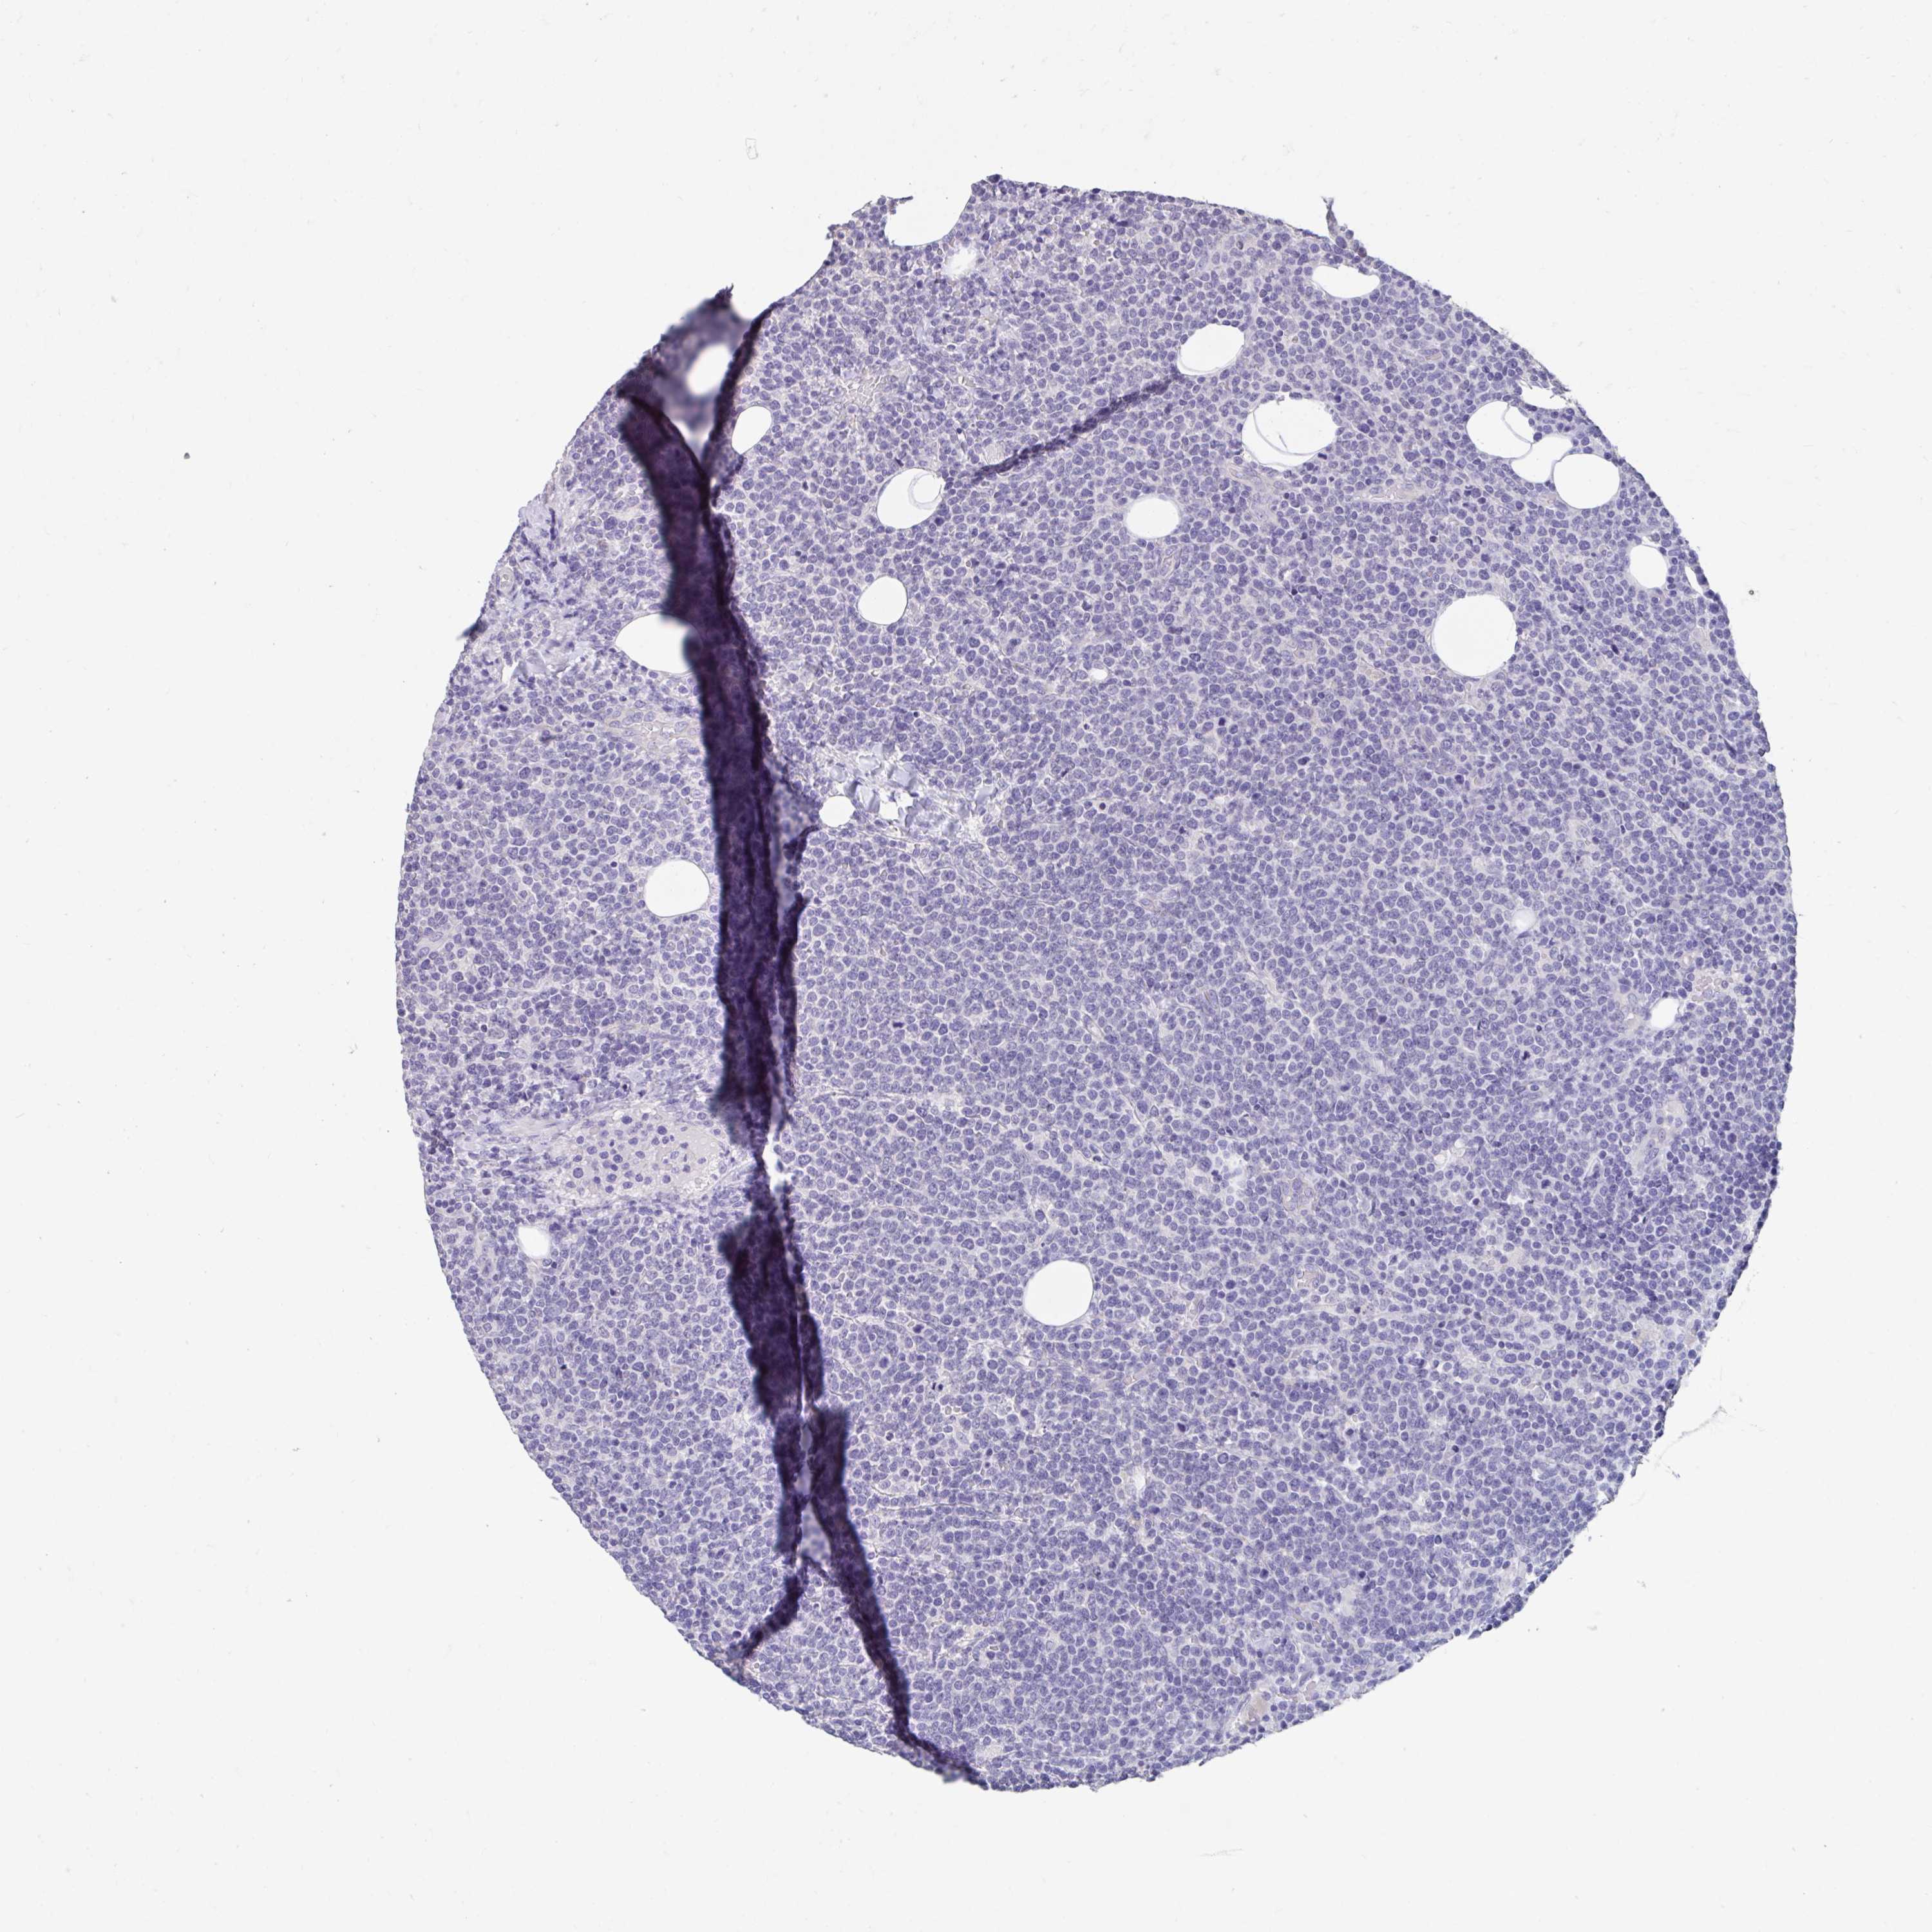

CANCER LYMPHOMA Show tissue menu

LYMPHOMA - Protein expressioni

A mouse-over function shows sample information and annotation data. Click on an image to view it in a full screen mode. Samples can be filtered based on level of antibody staining by selecting one or several of the following categories: high, medium, low and not detected. The assay and annotation is described here.

Each image is clickable and will lead to virtual microscopy that enables deeper exploration of all samples and also displays staining intensity scores, fraction scores and subcellular localization as well as patient and tissue information for each sample.

Antibody HPA055135

Staining

High

Medium

Low

Not detected

Intensity

Strong

Moderate

Weak

Negative

Quantity

>75%

75%-25%

<25%

None

Location

Nuclear

Cytoplasmic/membranous

Cytoplasmic/membranous,nuclear

Malignant lymphoma, non-Hodgkin's type, Low grade

Malignant lymphoma, non-Hodgkin's type, High grade

Hodgkin's disease, NOS

Hodgkin's lymphoma, nodular sclerosis